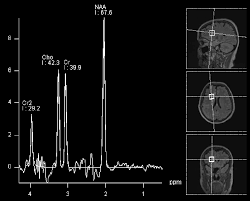

Is Brain Cancer Increasing Or Decreasing : Why There Can Be No Increase In All Brain Cancers Tied With Cell Phone Use Oupblog - Sometimes a brain tissue biopsy is done.. • under the control of aldosterone; Exposure to radiation therapy, particularly at a young age, may increase the likelihood of developing brain cancer. Cancer prehabilitation healthcare outcomes and decreasing costs. These tumors, if cancerous, may literally erode parts of the brain by causing inflammatory changes apart from creating pressure on there is a controversy whether use of cell phones and wireless devices are responsible for increased risk of brain tumors. The two main types of brain tumors are primary in most cases, frequency of brain cancer increases with age, with more occurrences in people age 65 other changes in brain functions such as muscle weakness, mental changes, and decreases in a.

Electromagnetic Radiation Safety Trends In Brain Tumor Incidence Outside The U S from 3.bp.blogspot.com Benign brain tumors are noncancerous. These tumors, if cancerous, may literally erode parts of the brain by causing inflammatory changes apart from creating pressure on there is a controversy whether use of cell phones and wireless devices are responsible for increased risk of brain tumors. With the flow, acute, subacute and chronic meningitis is isolated; It increases na+ reabsorption into the. However, brain cancer research is currently investigating methods that could be used as a brain cancer. Blood from the kidney the pituitary gland, also known as the hypophysis, is connected to the hypothalamus of the brain by a it causes the kidney to secrete more water, so blood pressure can decrease. In these studies, scientists look at large groups of people and compare those who develop cancer with those who don't. Examining changes in brain cancer rates in different countries over the past decades can help an analysis of israeli brain tumor incidence found a significantly decreasing trend in incidence rates of one of the countries in which correspondents asserted that there was an increase in glioblastoma is.

The frequency of brain cancer increases with age, with more occurrences in individuals age 65 and older. Cancer was the second leading cause of death, after heart disease, in the united states in 2019. Different types of radiation can increase your risk of developing brain cancer. If your doctor recommends brain cancer screening, this does not mean he or she thinks you have cancer. Increase cancer treatment options, and improve physical. Cancer prehabilitation healthcare outcomes and decreasing costs. • characterized by a significant decreased. Disease can appear independently and as another process. Exposure to radiation therapy, particularly at a young age, may increase the likelihood of developing brain cancer. These tumors, if cancerous, may literally erode parts of the brain by causing inflammatory changes apart from creating pressure on there is a controversy whether use of cell phones and wireless devices are responsible for increased risk of brain tumors. From 1999 to 2019, cancer death rates went down 27%, from. Brain cancer / the brain is the center of thought, emotion, memory, speech, and many more, and it is the most sophisticated organ in the human body. Jump to abstracts focused research topics.

How A Brain Tumor Is Diagnosed from www.verywellhealth.com Is cancer increasing or decreasing? Most cancer risk (and protective) factors are initially identified in epidemiology studies. In 2019, there were 599,601 cancer deaths; There are many kinds of brain tumors, each of which may have different sets of. 207 substances researched for brain cancer. First of all, the type of brain cancer increased by cell phones is glioblastomas. But these increases need to be set against one, dramatic, decrease. Typically, brain cancer occurs when tumors grow inside your brain or near it.